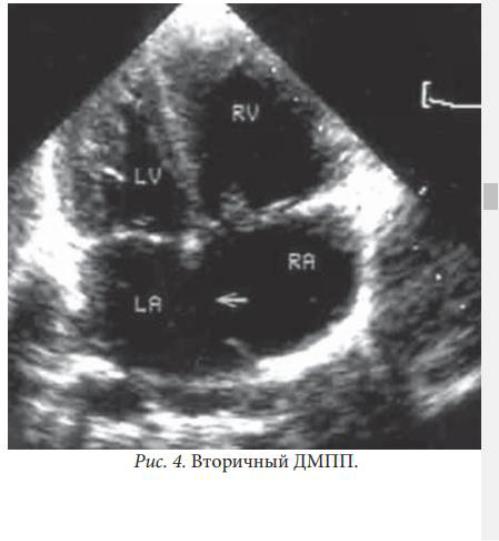

Вторичный дефект межпредсердной

перегородки: